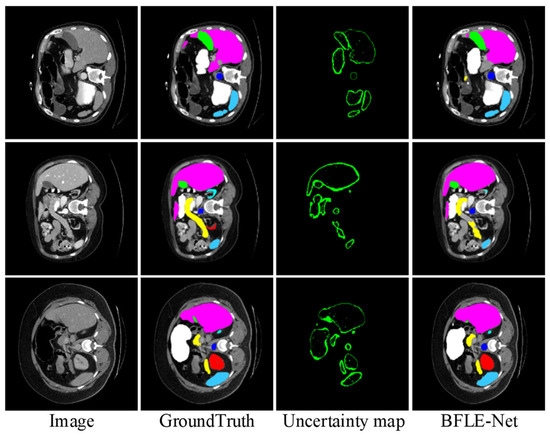

To further validate the effectiveness of the proposed BLM module, we visualize the uncertainty map in the BLM of the last layer at the decoder end, visualizing the uncertainty map side by side with the predicted segmentation mask and ground truth. As shown in Figure 10, regions with high uncertainty values primarily appear at object boundaries or in ambiguous areas (such as weak edges or occluded structures), where pixel-level classification is inherently more challenging. These observations align with the design intent of BLM, which aims to allocate more attention to uncertain boundary regions. Based on the final results, the segmentation accuracy for the target boundary blurred areas achieved a relatively satisfactory effect.

Figure 10. Visualization of uncertainty map functions and their impact on network attention.